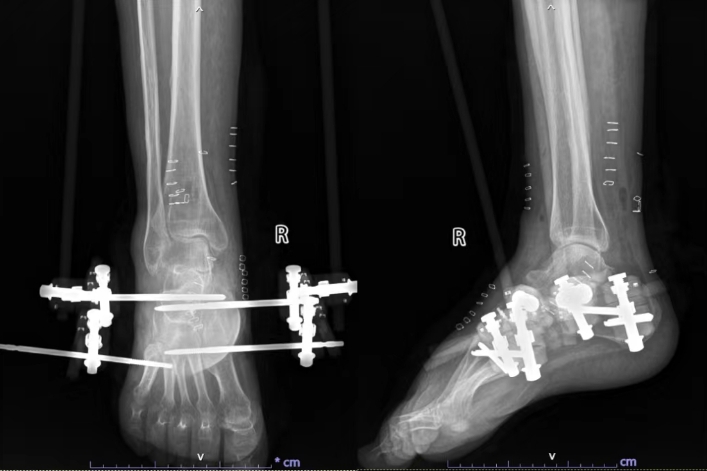

手术当天,骨外科副主任曾舸、高春生用时两个小时为患者顺利实施手术,患者平安返回病房。复查X线片显示,患者马蹄内翻已完全矫正,以后可以正常行走了。

术后X线片